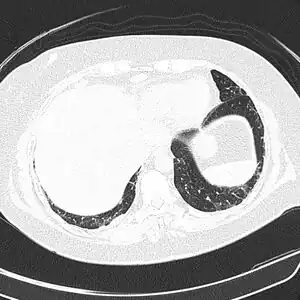

CT scan lungs: mass in right upper lobe

Lung

Cryptococcus (both C. neoformans and C. gattii) plays a common role in pulmonary invasive mycosis seen in adults with HIV and other immunocompromised conditions.[15] It also affects healthy adults at a much lower frequency and severity as healthy hosts may have no or mild symptoms.[16] Immune-competent hosts may not seek or require treatment, but careful observation may be important.[17] Cryptococcal pneumonia has a potential to disseminate to the central nervous system (CNS) especially in immunocompromised individuals.[18]

Pulmonary cryptococcosis has a worldwide distribution and is commonly underdiagnosed due to limitations in diagnostic capabilities. Since pulmonary nodules are its most common radiological feature, it can clinically and radiologically mimic lung cancer, TB, and other pulmonary mycoses. The sensitivity of cultures and the Cryptococcal (CrAg) antigen with lateral flow device on serum are rarely positive in the absence of disseminated disease.[15] Moreover, pulmonary cryptococcosis worsen the prognosis of cryptococcal meningitis.[15]